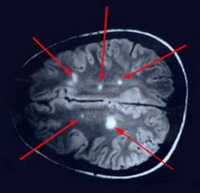

Esclerosis múltiple

Es una enfermedad crónica del SNC que consiste en la aparición continua de focos de inflamación autolimitados en zonas de la sustancia blanca (parte del SNC cubierta de mielina) que pueden dejar como secuela la desmielinización definitiva de esa zona. Esta enfermedad se produce cuando el sistema inmune de una persona ataca sus propias fibras nerviosas mielinizadas, destruyendo sus propiedades de conducción. Si los nervios dañados inervan músculos, el movimiento se verá perjudicado.